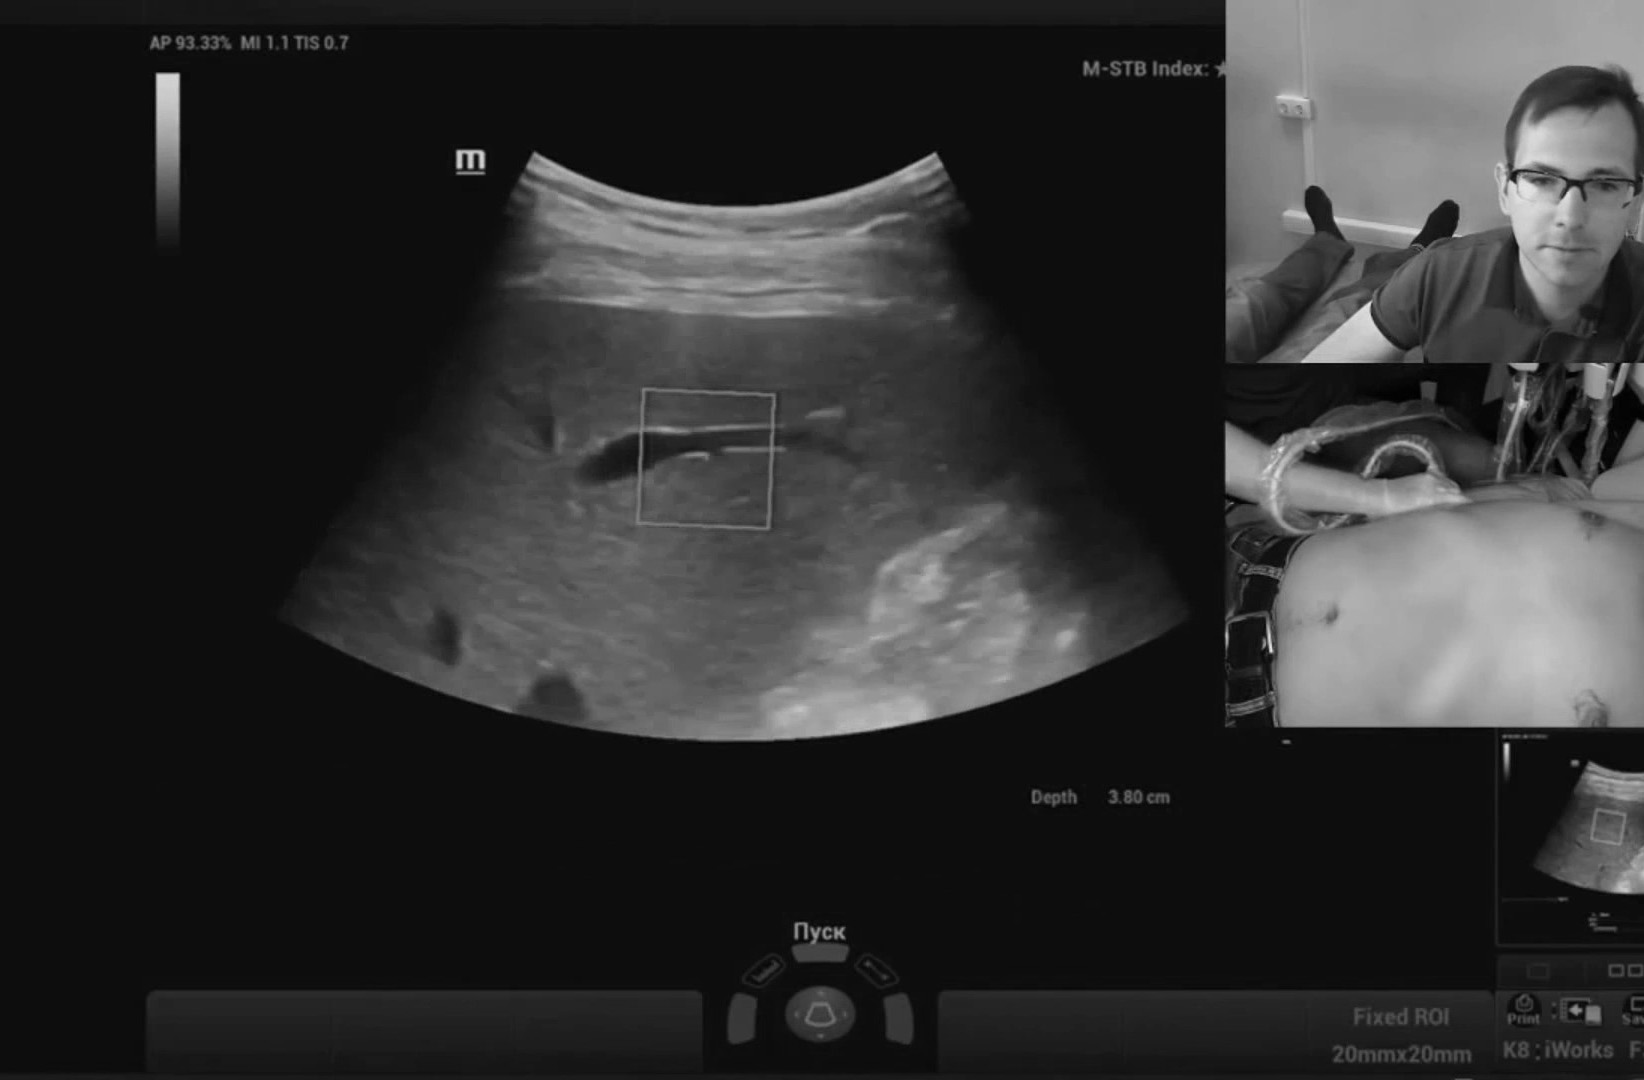

Обзор УЗИ: Отзыв о работе ультразвукового аппарата Mindray Resona 6

Работа с видео петлями реализована в полном объеме, то есть можно снять видео без оптимизации и отпустить пациента, оптимизацию провести уже на отснятых петлях в удобное время. Наличие эластографии сдвиговой волны периодически заставляет забыть, что я врач УЗД, бывают дни, когда делаешь одну эластографию печени. Очень популярная методика.

Осмотр брюшной полости в педиатрии линейным датчиком с низкими частотами - без проблем, сигнал не затухает. Живот просвечивает насквозь, стенки кишечника и желудка видны четко и детально. Поиск лимфоузлов брыжейки - без проблем. Кардиопакеты полные с возможностью стрейна, тканевого допплера, авторасчета объема и фракции выброса желудочков. Измеряемые объемы автоматически индексируются на площадь поверхности тела.